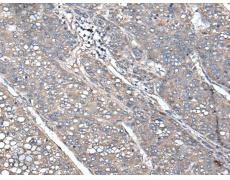

IHC positive control: |

Human liver cancer and Human lung cancer |